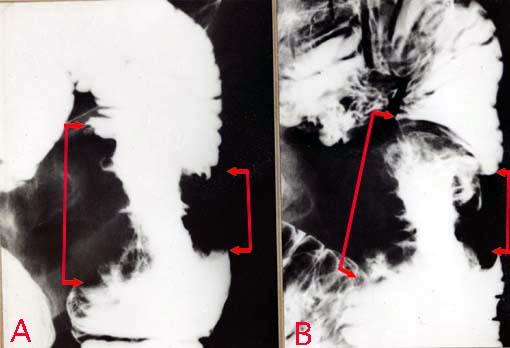

clasificación del pacienteTumor de tipo Metastásico/

parte(separada por órganos)intestino delgado/yeyuno

método de exámenRayos X

clasificación ectoscópica de tumoresTipo 5(no clasificable)/

diámetro mayor del tumor40 -

grado de penetracións(a)